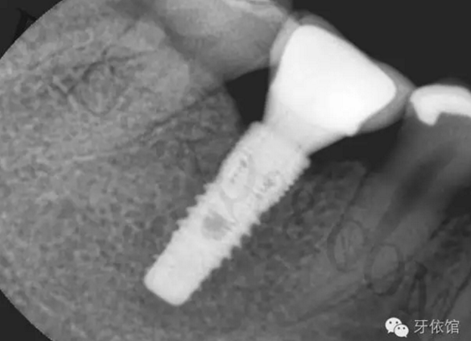

再將烤瓷冠就位,拍X光片,檢查烤瓷牙與基臺之間是否密貼。

粘冠。